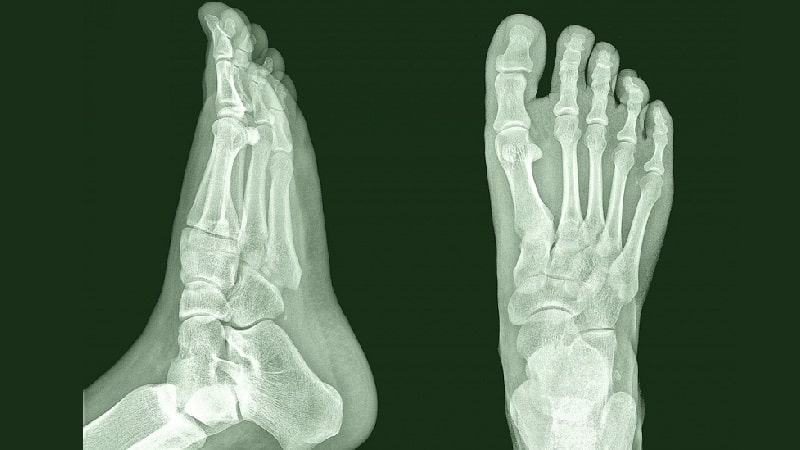

Кости стопы

Изучим анатомическую структуру костей стопы. На рентгеновском снимке четко видно, из каких элементов состоит эта часть ноги. Стопа делится на три основные секции: предплюсну, плюсну и пальцы.

Стопа человека представляет собой сложную анатомическую структуру, состоящую из 26 костей, 33 суставов и более 100 связок и мышц. Врачи подчеркивают, что такая сложность обеспечивает стопе гибкость и устойчивость, позволяя эффективно выполнять функции опоры и передвижения. Каждый элемент стопы играет свою роль: например, своды обеспечивают амортизацию при ходьбе и беге, а пальцы помогают сохранять равновесие. Специалисты отмечают, что здоровье стопы напрямую влияет на общее состояние опорно-двигательного аппарата. Неправильная обувь или травмы могут привести к различным заболеваниям, таким как плоскостопие или артрит. Поэтому регулярные осмотры и забота о стопах являются важными аспектами поддержания здоровья.